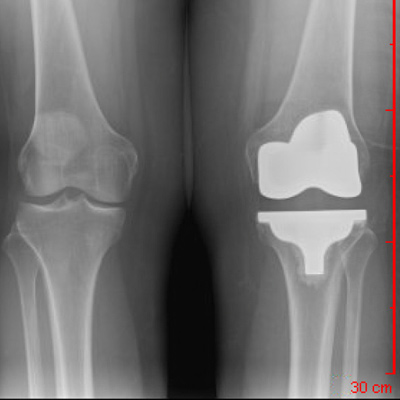

Anterior-Posterior View Total Knee Replacement

R knee: Mechanical Alignment

L knee: Kinematic Alignment